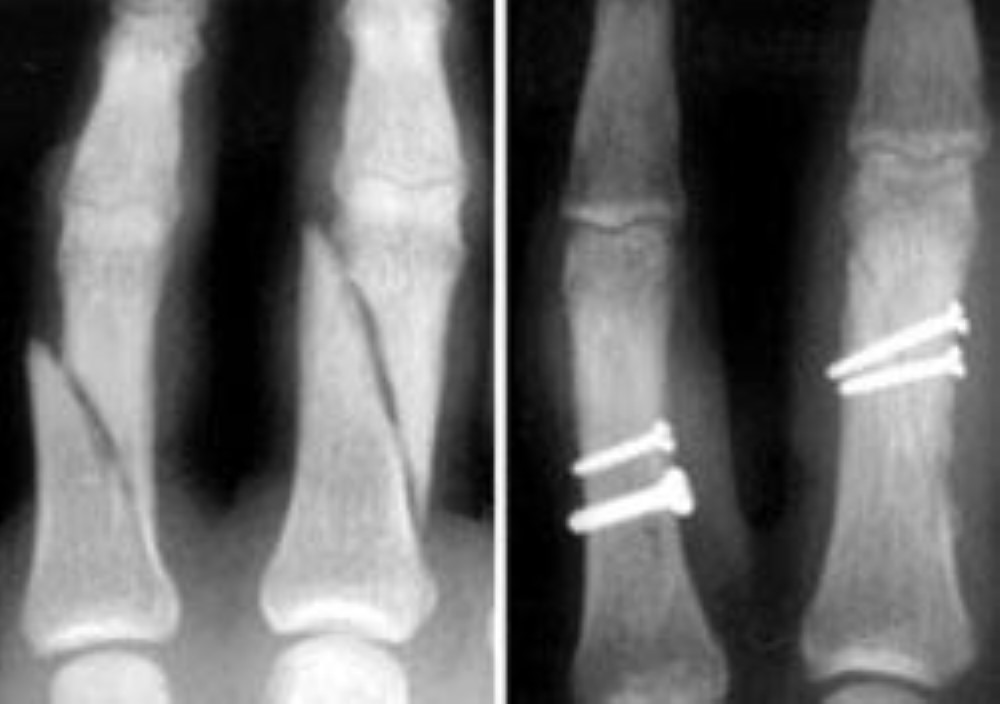

From www.researchgate.net

Stable, undisplaced spiral phalanx of the index finger (Case 2 Spiral Finger Fracture A spiral fracture is a bone fracture caused by a twisting force that breaks the bone in half. Learn about the affected body parts, severity, treatment options, and. Find out how to prevent complications and restore finger function with splints, surgery, or therapy. A spiral fracture is a broken bone pattern that wraps around the bone, caused by a twisting. Spiral Finger Fracture.

Stable, undisplaced spiral phalanx of the index finger (Case 2 Spiral Finger Fracture It is a serious injury that often. Learn about the affected body parts, severity, treatment options, and. Learn about the causes, symptoms, and treatment options for different types of finger fractures, including intraarticular fractures that extend into the joint. It is most common in the tibia, or shinbone, and can be stable or displaced. A spiral fracture is a complete. Spiral Finger Fracture.